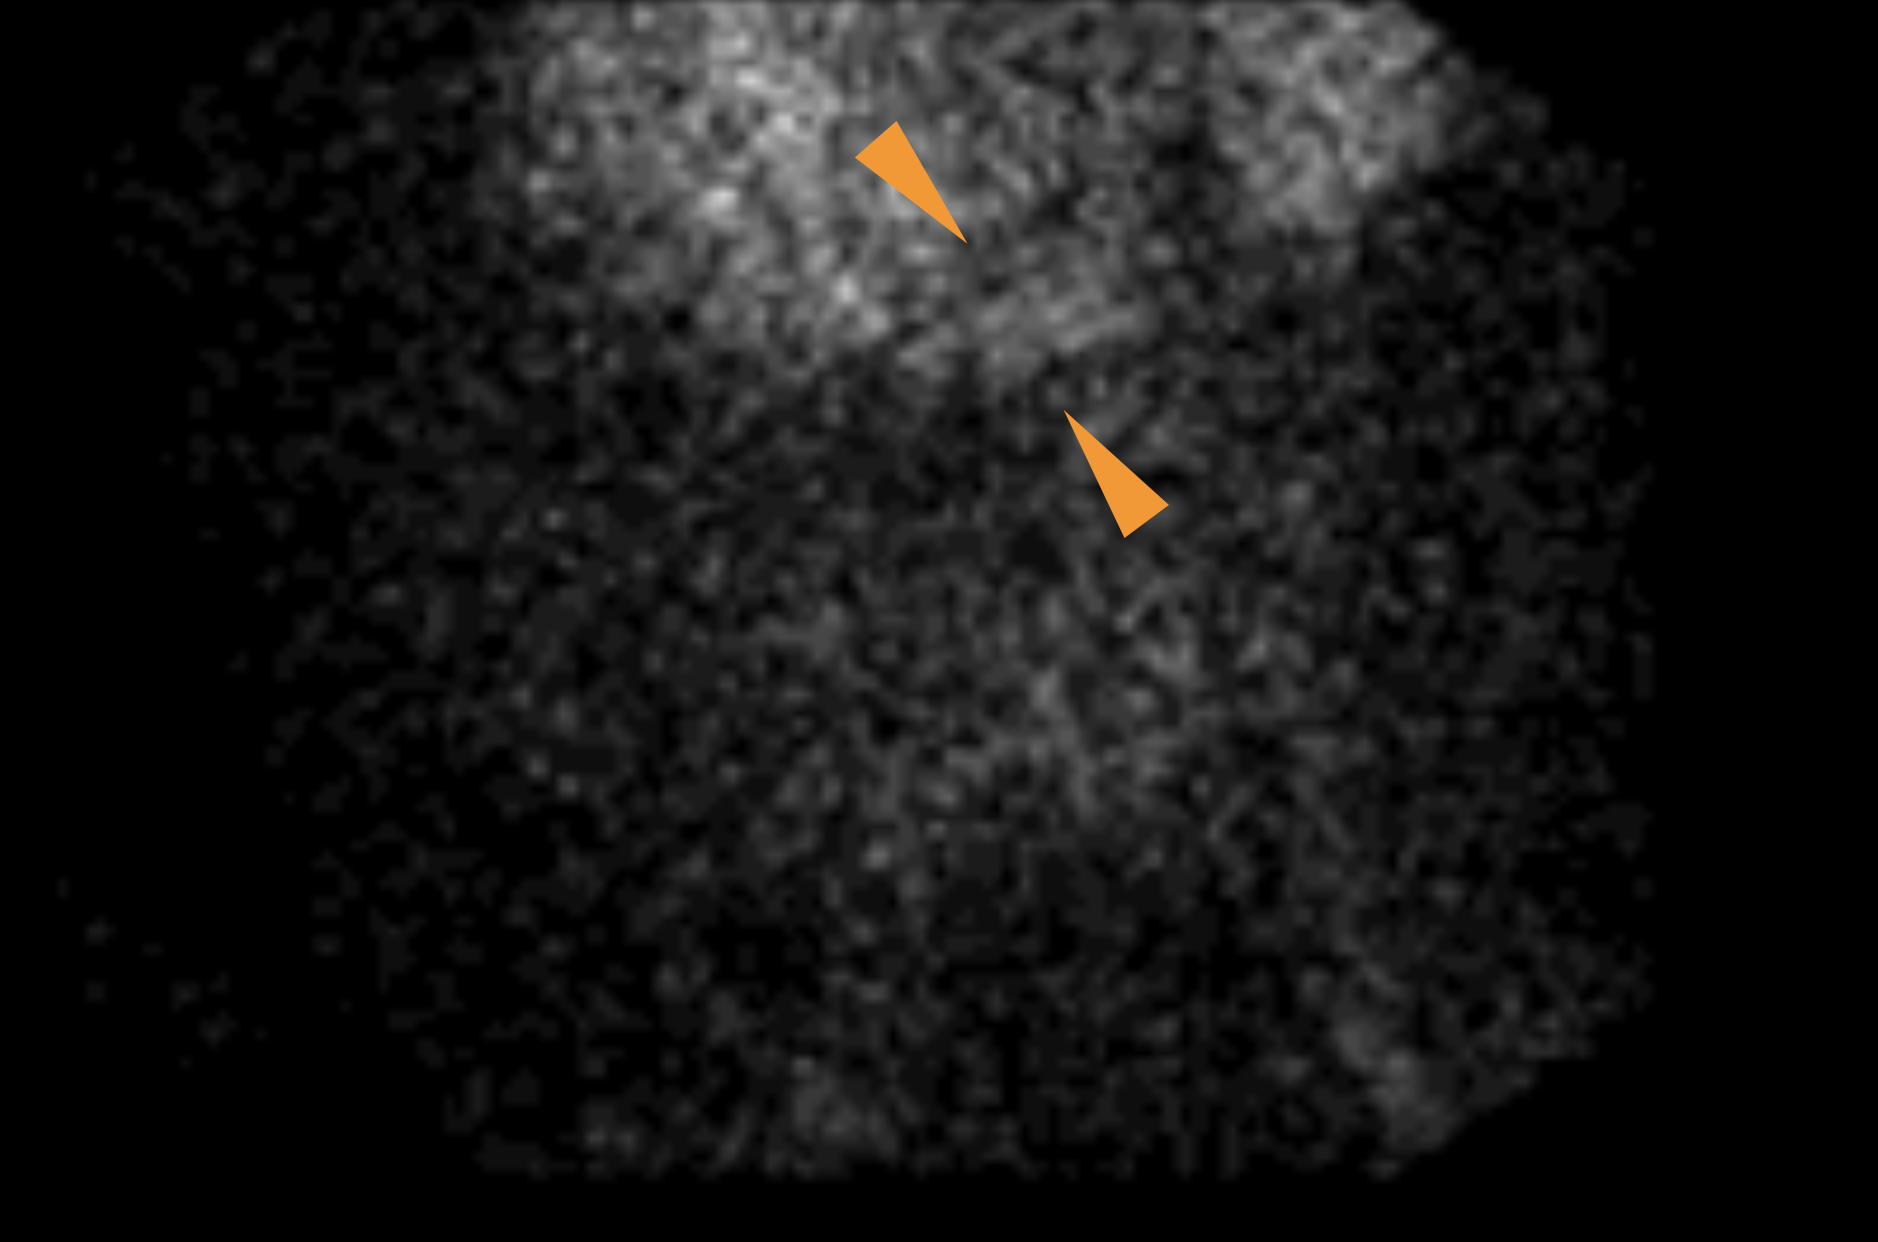

Age: 54

Sex: Male

Indication: Tarry stools, hypotension

Radiotracer: Tc99m labeled RBCs

Sample ReportNo evidence of active GI bleeding during the course of this study.